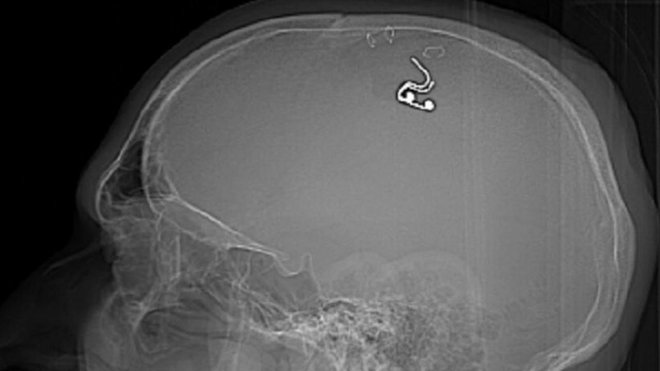

A Russian man named Michael Raduga implanted a chip in his head in an attempt to control his dreams. Raduga said he spent hours watching videos online showing how neurosurgeons work before drilling a hole in his skull and inserting the electrode.

The surgery nearly killed Raduga, who said he lost a lot of blood. However, he claims that the results are promising and could lead to future dream control technologies.